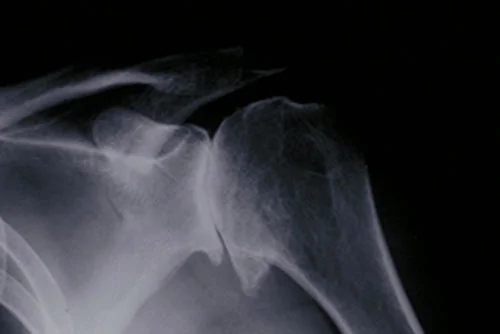

Shoulder arthritis is diagnosed by shoulder specialists, like myself, by a combination of the medical history, physical examination, and x-rays of the shoulder.  X-rays of the shoulder normally show significant narrowing of the joint space and formation of bone spurs.